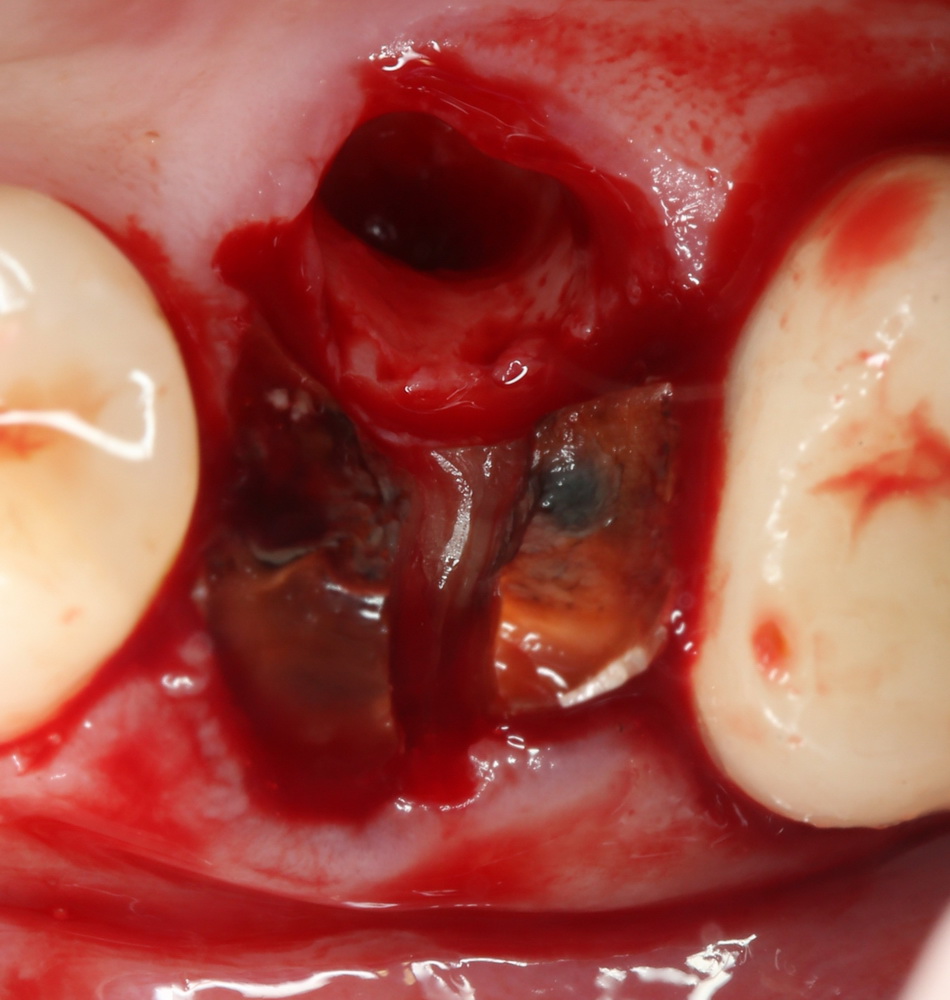

Пример второй. На этот раз — мужчина в самом расцвете сил.

Нам пришлось удалить 15 зуб из-за повреждения его корня. И, к сожалению, не было возможности делать немедленную имплантацию, поскольку расстояние от верхушки корня до дна гайморовой пазухи составляло менее миллиметра, а сам зуб однокорневой, и корень достаточно большой — другими словами, достаточного объема кости для стабилизации импланта нет.

Что делать? Оставлять лунку после удаления и ничего не делать — это почти 100% атрофия. Следовательно мы создадим себе последующую работу, а пациенту — расходы на имплантацию. Мы решили попробовать законсервировать лунку зуба, причем, в данном случае речь еще шла о профилактике ороантральной перфорации.

Очень аккуратно удалили зуб. Убрали из лунки все грануляции. В область верхушки корня зуба — Neocones, остальная часть альвеолы — Bioss Collagen. Сама лунка запечатывается Mucograft Seal:

Который подшивается к ее краям: